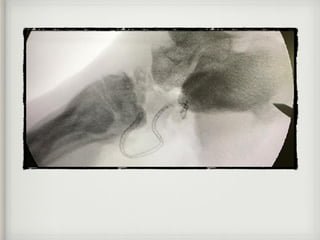

13.05.21

27.05.21